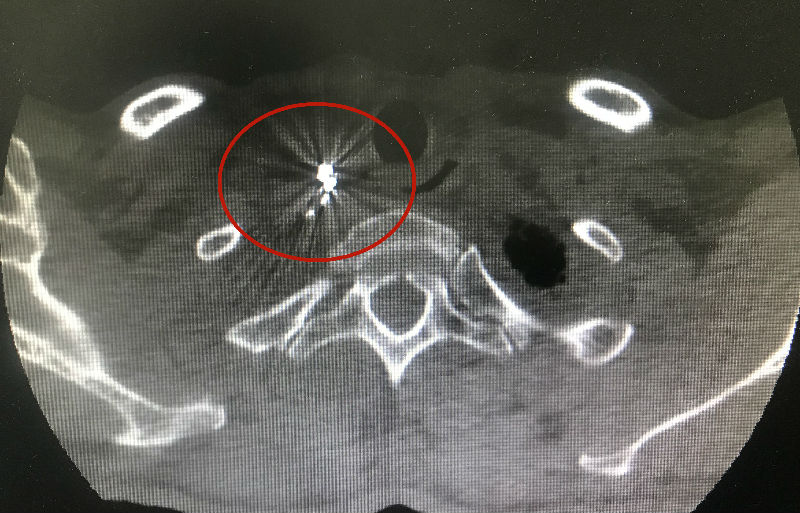

治疗方案确定后,曹旸在CT引导下准确将多颗碘125粒子植入到了肿瘤部位,对肿瘤细胞及组织形成局部持续辐射,可提高靶区的照射量,有效抑制肿瘤细胞的分裂和再增殖,对周围组织脏器及正常细胞损伤轻微,精确性高,并发症较少。

粒子植入后的状态

术前肿块大小为18x23x19mm

系统治疗后肿块大小为13x10x9mm